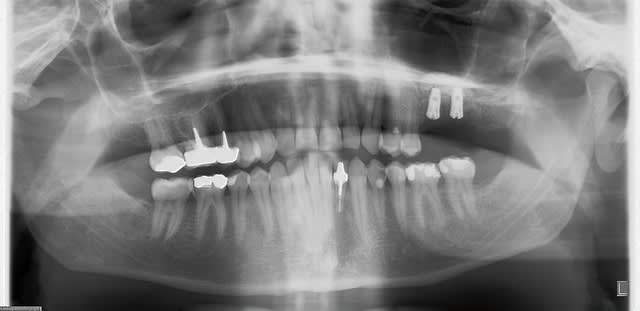

C'est une technique que je pratique très souvent et qui me donne entière satisfaction. Pour ceux qui se demandent à quoi cela ressemble, je poste un exemple.

Dans la littérature il n'y a pas vraiment d'étude RCT analysant juste cette technique chirurgicale. Cependant cette approche est largement utilisée dans les études sur les sinus lift réalisées par l'équipe de Stefan Lundgren & Lasse Sennerby en Suède, l'équipe de Ferrari Marco en Italie et celle de Sohn en Corée.

Je n'ai à ce jour eu aucune complication dûe à une nécrose du volet osseux (risque évoqué par Mac).

Merci Olivier de ta réponse sans ambiguité joliment iconographiée.